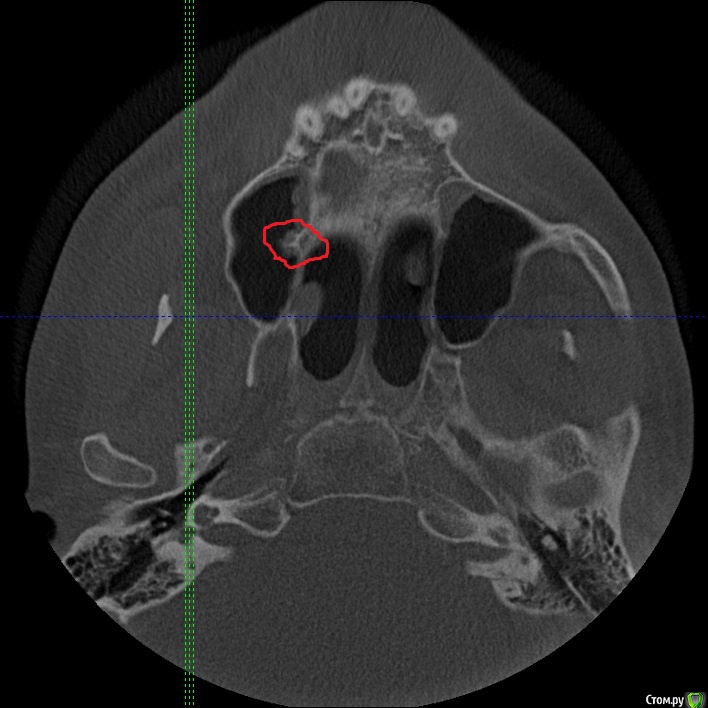

Секатор Опубликовано 4 октября, 2015 Поделиться Опубликовано 4 октября, 2015 (изменено) Здраствуйте,уже писал,но проблем много,но сча есть снимки зд(ссори за флуд).Начну издалека года два летом примерно неделю начили болеть зубы справа с отдованием в ухо и висок,оперативно ничего не делал(спас ал алкоголь),но я решил,что это 8-ки,и за зиму последнию все удалил,но отдования в висок и болезненность уха осталось,много времени прошло после удаления.Напряжение у виска и в области уха,взгляните на мою 6 справа,дно пазухи деформировано под её давлением,боли в области зуба нет-она причина?По лор все чисто,как будто болит зуб отдовая в ухо и висок,но без боли в области челюсти.Ближе к внутренней стенки пазухи и заходя на неё сформирован остроконечный конус дном пазухи,вследствии давлении корня зуба. Изменено 4 октября, 2015 пользователем Секатор 1 Ссылка на комментарий

Секатор Опубликовано 15 октября, 2015 Автор Поделиться Опубликовано 15 октября, 2015 (изменено) И,ещё раз прошу взглянуть смотрите,как деформирована внутреннеяя стенка пазухи зубом,у дна.Может корень подцепил,стенку пазухи? Изменено 15 октября, 2015 пользователем Секатор Ссылка на комментарий

kozloff Опубликовано 16 октября, 2015 Поделиться Опубликовано 16 октября, 2015 Поймите, с пазухой все хорошо, просто отлично, и с корнем верхнего зуба тоже. Удаляйте злосчастный мышьяк, пломбируйте каналы в пульпитом зубе и будет вам счастье! Ссылка на комментарий